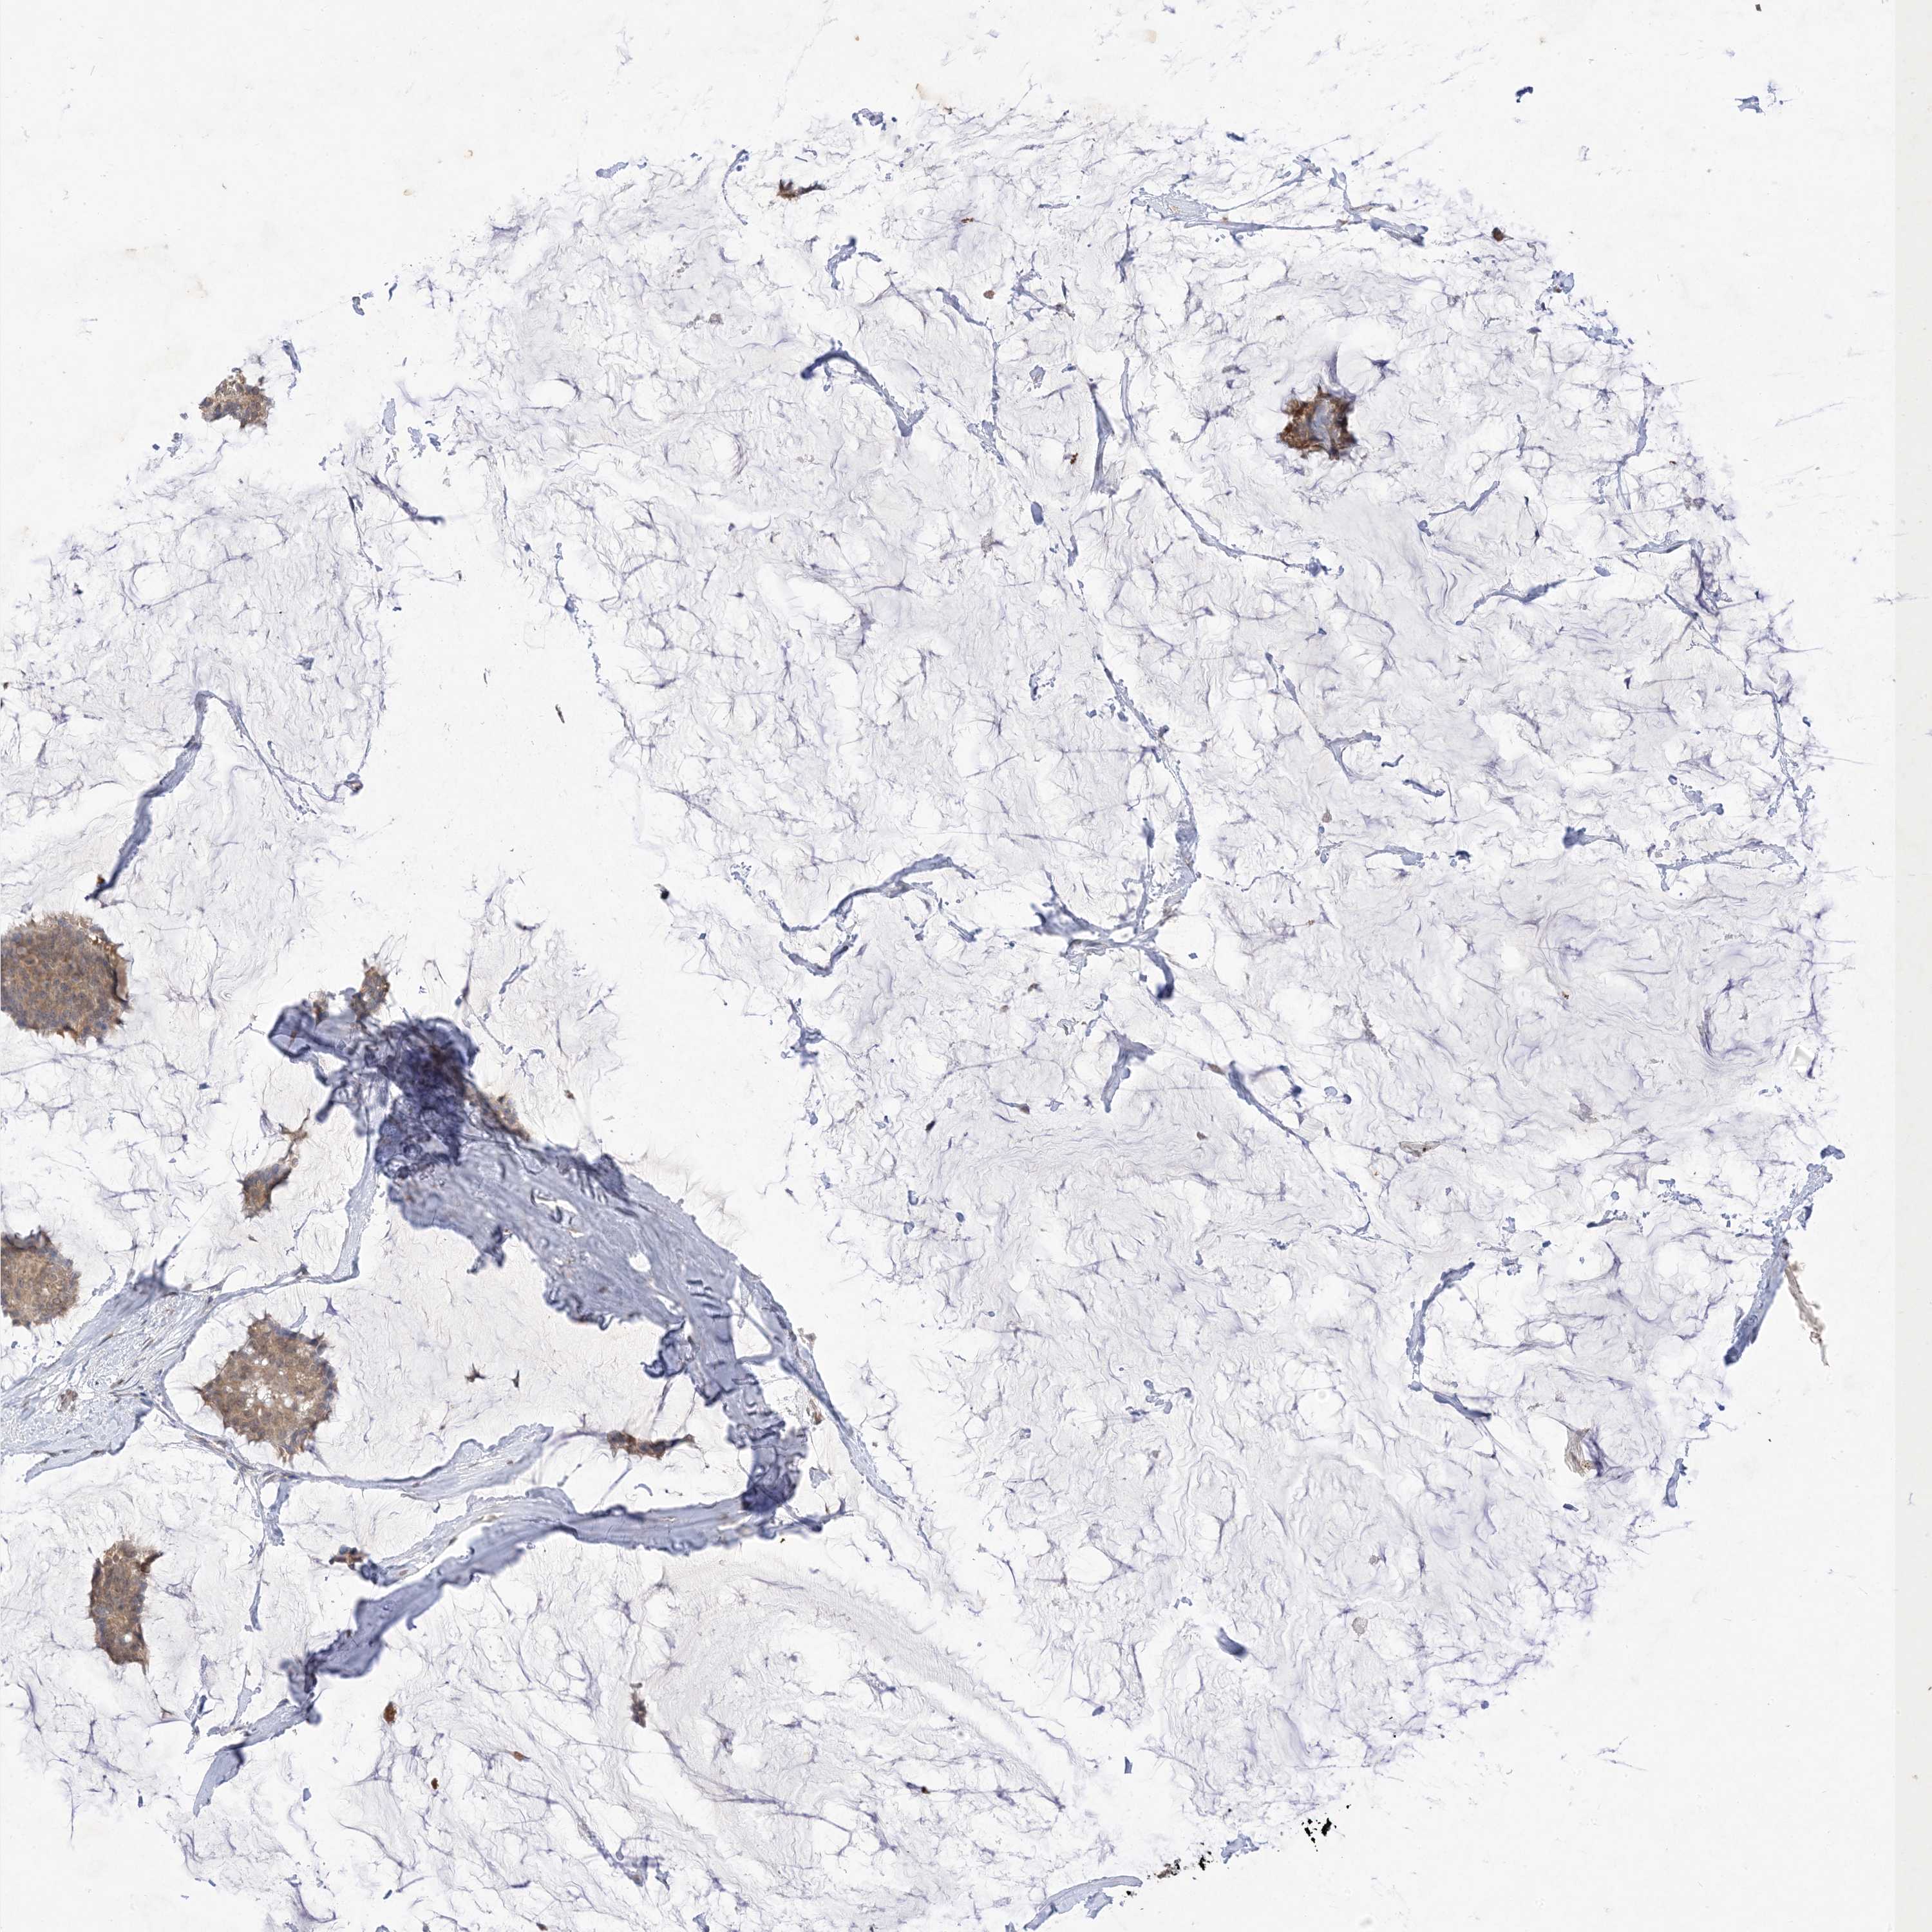

CANCER BREAST CANCER Show tissue menu

BRCA TCGA BRCA VALIDATION PROTEIN EXPRESSION